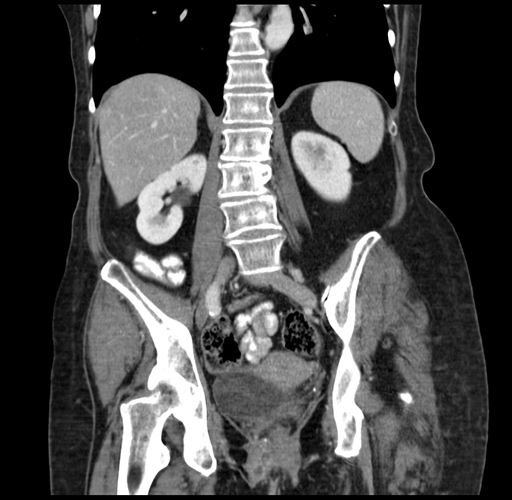

Axial Venous